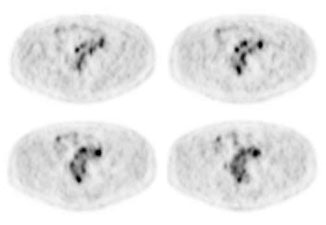

Hyperinsulinemia: The patient below had

a normal glucose level and was injected for an FDG PET

scan. Imaging revealed intense cardiac uptake and a large

about of muscular activity. The findings are consistent

with a hyperinsulinemic state and the patient subsequently

admitted to eating a small breakfast. |